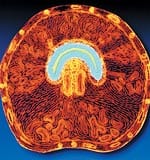

The African cherry tree, pygeum africanum, is an evergreen found at higher elevations across Africa. Its medicinal use dates to the 1700s, when tribes in southern Africa taught early explorers how to use the tree’s bark to treat bladder discomfort.1 Pygeum extract has been used in Europe to treat benign prostatic hyperplasia since the 1960s, and is currently the most commonly used therapeutic for this condition in France.2 Benign prostatic hyperplasia affects approximately 50% of men aged 51-60, and up to 90% of men over the age of 80. This condition causes the prostate gland to enlarge, constricting the urethra and making it difficult for the bladder to empty. Symptoms include reduced urine stream, frequent urination (especially at night), urinary urgency, leaking, and urinary retention. Severe benign prostatic hyperplasia can have serious long-term health effects, such as urinary tract infection, bladder or kidney damage, bladder stones, pain during sexual intercourse, and incontinence. Therapies to treat this condition include pharmaceutical drugs such as Proscar®, Hytrin®, and Flomax®, as well as non-surgical and surgical options. However, all of these remedies have associated side effects. Clinical studies suggest that pygeum bark extract is effective in reducing symptoms of benign prostatic hyperplasia, with few side effects.3,4 Benign prostatic hyperplasia’s cause is not fully known or understood. One theory is that the conversion of testosterone to dihydrotestosterone via the enzyme 5-alpha-reductase contributes to prostate enlargement.5 In addition, as men age, they often experience an increase in levels of estrogen relative to testosterone, indicating that estrogen may be involved in the development of this condition. In one study, extracts of pygeum and nettle root partially blocked the action of two enzymes, aromatase and 5-alpha-reductase, that are involved in the production of estrogen and dihydrotestosterone, respectively. Pygeum showed much higher efficacy at lower doses than did nettle root, but the combination of both herbs was significantly more effective than either alone in blocking the aromatase enzyme.6 How Does Pygeum Work?Pygeum bark contains numerous beneficial constituents, including phytosterols such as beta-sitosterols, which exhibit anti-inflammatory action by inhibiting the production of prostaglandins in the prostate. Other pygeum components in-clude ferulic esters, which reduce levels of prolactin (a hormone that promotes testosterone uptake in the prostate gland), and pentacyclic triterpenes, which inhibit an enzyme involved in inflammation and help reduce edema. Scientists believe that these phytochemicals work together to help counteract the structural and biochemical changes associated with benign prostatic hyperplasia.1,7 Pygeum may help to prevent the overgrowth of prostate cells that can contribute to benign prostatic hyperplasia. Research suggests that pygeum may do this by inhibiting basic fibroblast growth factor, a signaling biochemical involved in the development of benign prostatic hyperplasia.8 In a laboratory study, pygeum extract demonstrated an anti-proliferative effect on prostate cells derived from rats, which was in part mediated by inhibition of basic fibroblast growth factor.9

Enlargement of the prostate gland can obstruct bladder emptying, which can lead to cellular and functional changes in the bladder tissue. Studies of rabbits suggest that pre-treatment with pygeum helps to protect the bladder from developing contractile and biochemical dysfunctions induced by partial bladder outlet obstruction, possibly by protecting the bladder from ischemic injury.10,11 The investigators suggest that pygeum may work in both rabbits and humans to protect the bladder’s smooth muscle against cellular damage induced by obstructed flow.10 Reducing BPH SymptomsClinical trials suggest that pygeum can safely and effectively help to reduce the symptoms of benign prostatic hyperplasia. In a multicenter trial in Europe, 85 men with mild to moderate benign prostatic hyperplasia were given 50 mg of pygeum twice daily for two months. The study participants demonstrated a 40% decrease in the International Prostate Symptom Score, a subjective assessment of the severity of symptoms of benign prostatic hyperplasia. Furthermore, the pygeum-supplemented men reported a 32% decrease in frequency of nocturnal urination (nocturia) and a 31% improvement in quality of life. After the supplementation with pygeum ended, the patients were followed for one additional month. The benefits derived from the pygeum therapy continued even during this period without treatment, indicating a lasting therapeutic effect.12 In a larger placebo-controlled, double-blind study, 263 men received either 100 mg of pygeum or placebo daily for 60 days. The pygeum group demonstrated a 17.2% improvement in urinary flow, a 24.5% decrease in residual bladder volume, a 31% decrease in nocturia, and a 19.4% decrease in daytime urinary frequency. Overall, 66% of the pygeum group reported improvement, compared to only 31% of the placebo group.13 According to two separateliterature reviews, pygeum extract demonstrates statistically significant benefits for benign prostatic hyperplasia. The more recent review, conducted in 2000, analyzed studies dating from 1966 to 2000. In 18 randomized trials involving 1,562 men, pygeum provided significant improvement in combined outcome of urological symptoms and flow measures. Furthermore, men taking pygeum reported twice as much improvement in overall symptoms.3 An earlier literature review published in 1995 examined 12 clinical, placebo-controlled, double-blind studies, in which 358 patients received pygeum and 359 received placebo. Again, those consuming pygeum demonstrated statistically significant benefits compared to those receiving placebo.4